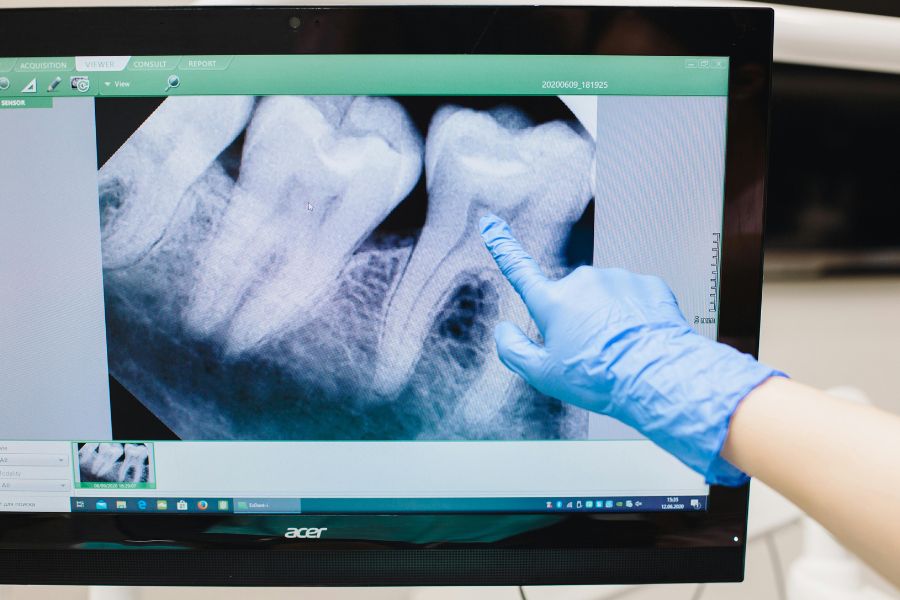

- Bước 1: Thăm khám và chụp X-quang

Bác sĩ kiểm tra tổng quát sức khỏe răng miệng và chụp phim X-quang để đánh giá vị trí, chiều hướng mọc. Bác sĩ xác định mức độ phức tạp của răng và chuẩn bị kế hoạch tiểu phẫu phù hợp.